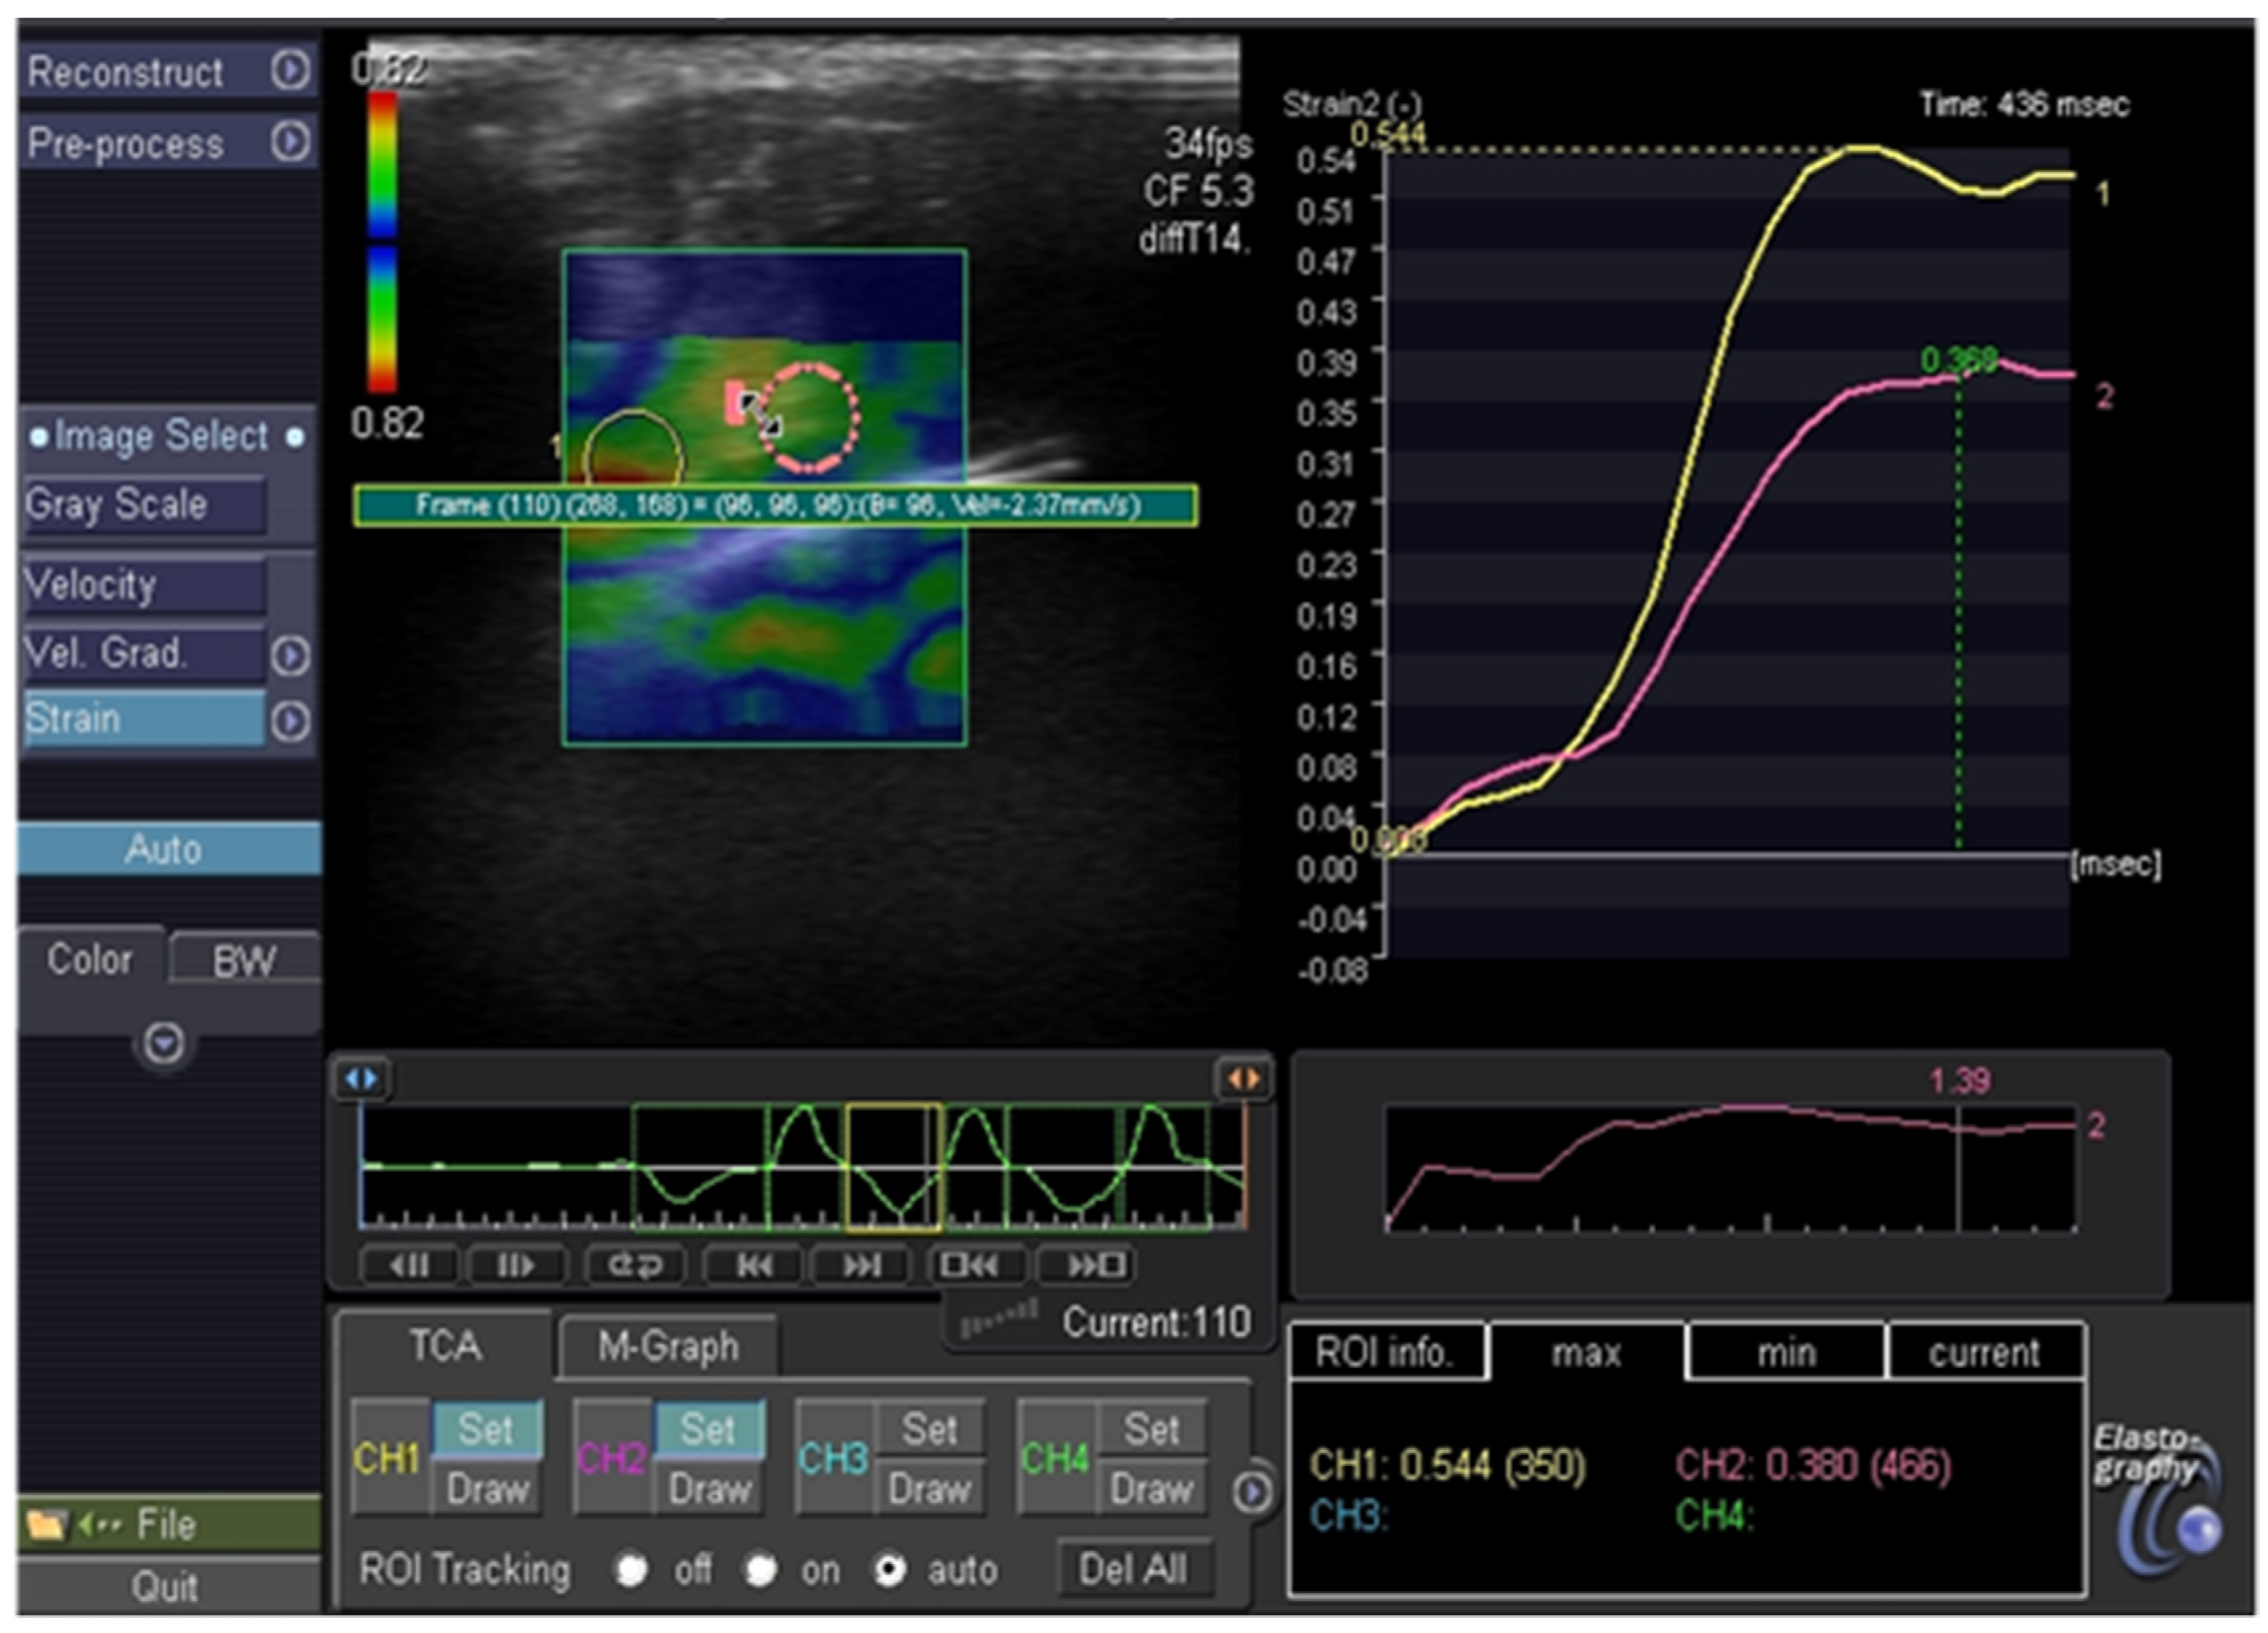

2.3. Thyroid Ultrasonography, Elastography and Fine Needle Aspiration Biopsy

3.1. Elastography